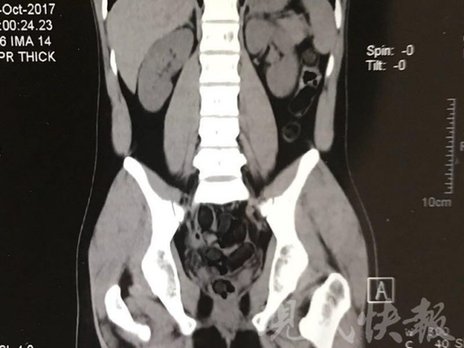

小伙體內(nèi)藏毒300余克 CT掃描圖密密麻麻

由于毒品在體內(nèi)一旦泄露有可能致命,警方第一時(shí)間將阿永帶到醫(yī)院進(jìn)行檢查。CT 掃描的結(jié)果顯示,阿永體內(nèi)布滿了密密麻麻的白色圓柱狀固體,就像一粒粒的蠶蛹。在南京市公安局鼓樓分局二板橋派出所,阿永分四次排出了毒品,毛重369.99克。經(jīng)訊問(wèn),阿永交代了自己全部的犯罪事實(shí)。目前,阿永已被刑事拘留。